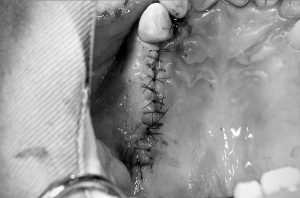

⑥縫合

術前の歯肉の状態と、縫合後の歯肉の状態にずれがないように、縫合する。